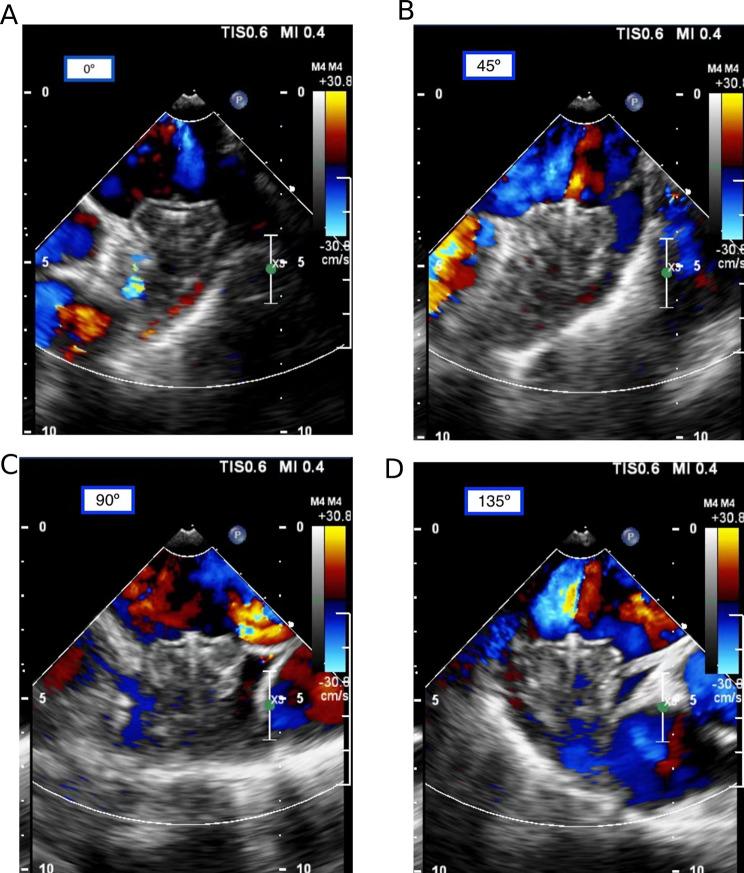

In this study, 68 AF patients who underwent successful implantation of the Watchman device without peri-device leak (PDL) during follow-up were included. The endothelialization status was assessed using Transesophageal echocardiography (TEE) and LAA computed tomography angiography (CTA) at 6 weeks and 6 months post-implantation. Adverse cerebro-cardiac events were documented at one-year follow-up. Baseline characteristics, including age, device sizes, and clinical indicators, were analyzed as potential predictors for IDE.

方法